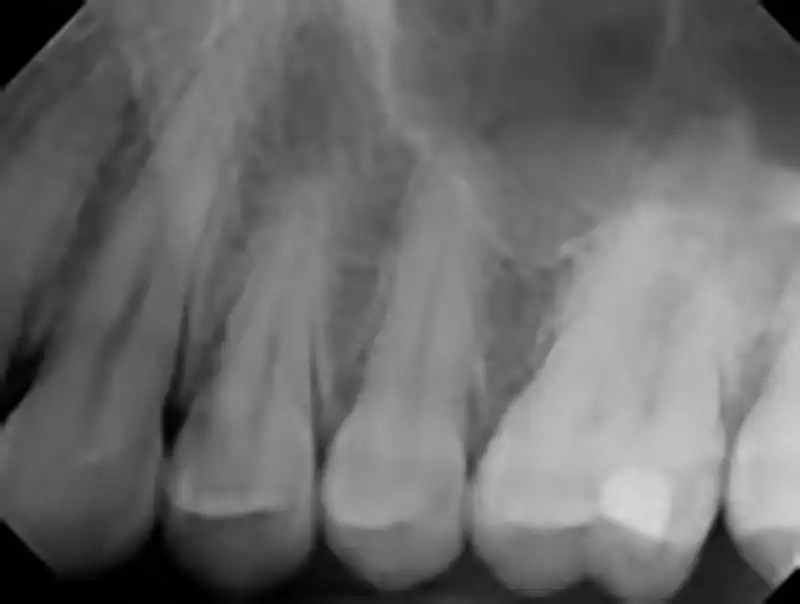

Periapical x ray Intraoral Dental Radiograph YouTube